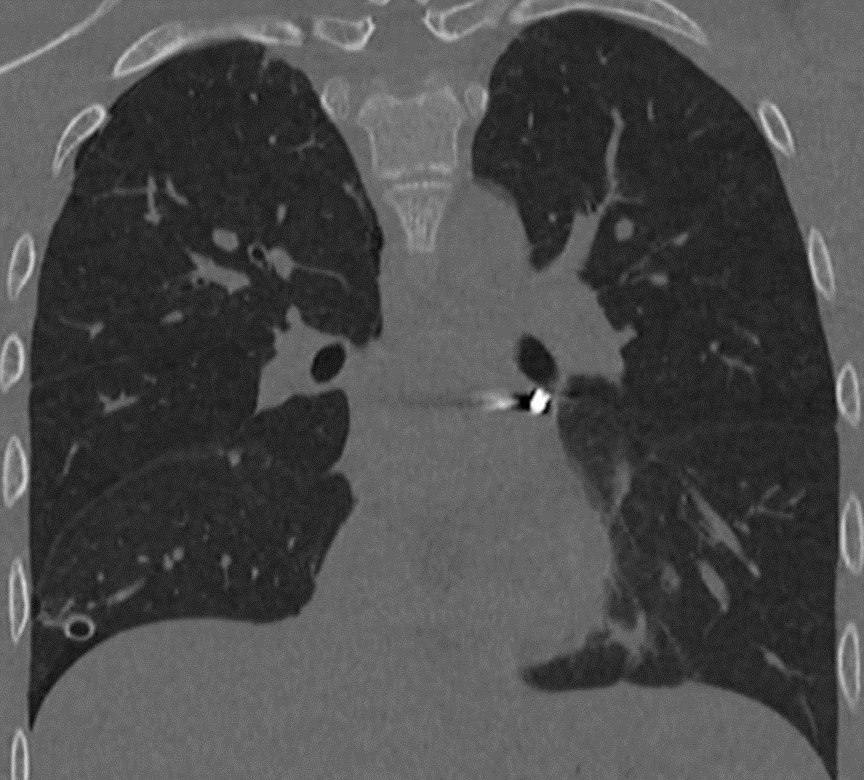

В Детский клинический центр им. Л.М. Рошаля экстренно поступил 16-летний подросток с проникающим ранением грудной клетки от пневматического ружья. Травму он получил во время неосторожной игры с друзьями. В ходе обследования врачи выявили крайне опасное расположение инородного тела в непосредственной близости от сердца: в полости перикарда — наружной оболочки сердца. Состояние пациента требовало немедленного хирургического вмешательства.

— Инородное тело мигрировало в опаснейшую зону — между легочными венами у задней поверхности предсердия. Мы выполнили малоинвазивную операцию со вскрытием перикарда, работая буквально в миллиметрах от жизненно важных структур. Особую сложность представляла необходимость манипулировать инструментами в условиях ограниченного обзора и постоянного движения сердца. В ходе вмешательства нам удалось извлечь инородное тело без единого разреза, — рассказал заведующий отделением детской хирургии №2 Никита Степаненко.